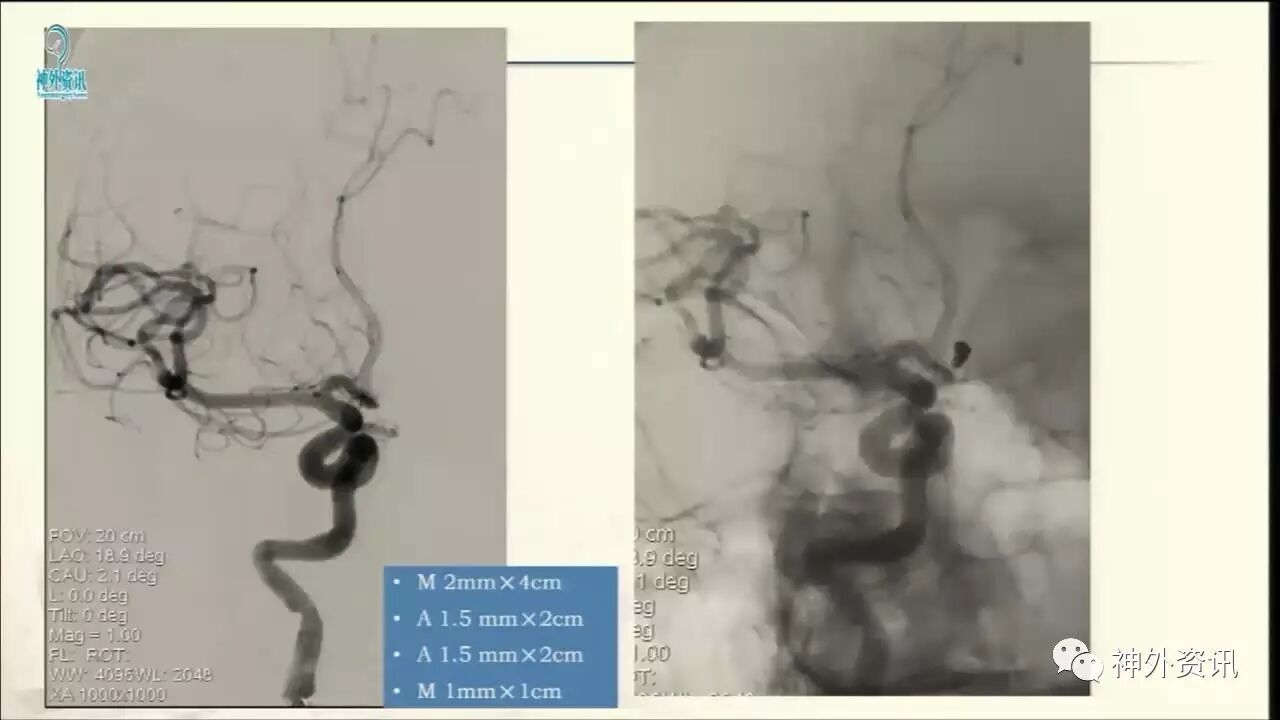

今天“神经介入专栏”为大家分享由上海交通大学医学院附属仁济医院神经外科副主任万杰清教授带来的“颅内小动脉瘤的介入治疗--GALAXY微弹簧圈是一种不错的选择”精彩讲课视频及PPT,欢迎观看、阅读。文章仅代表作者个人观点,如有不同见解,欢迎同道斧正!